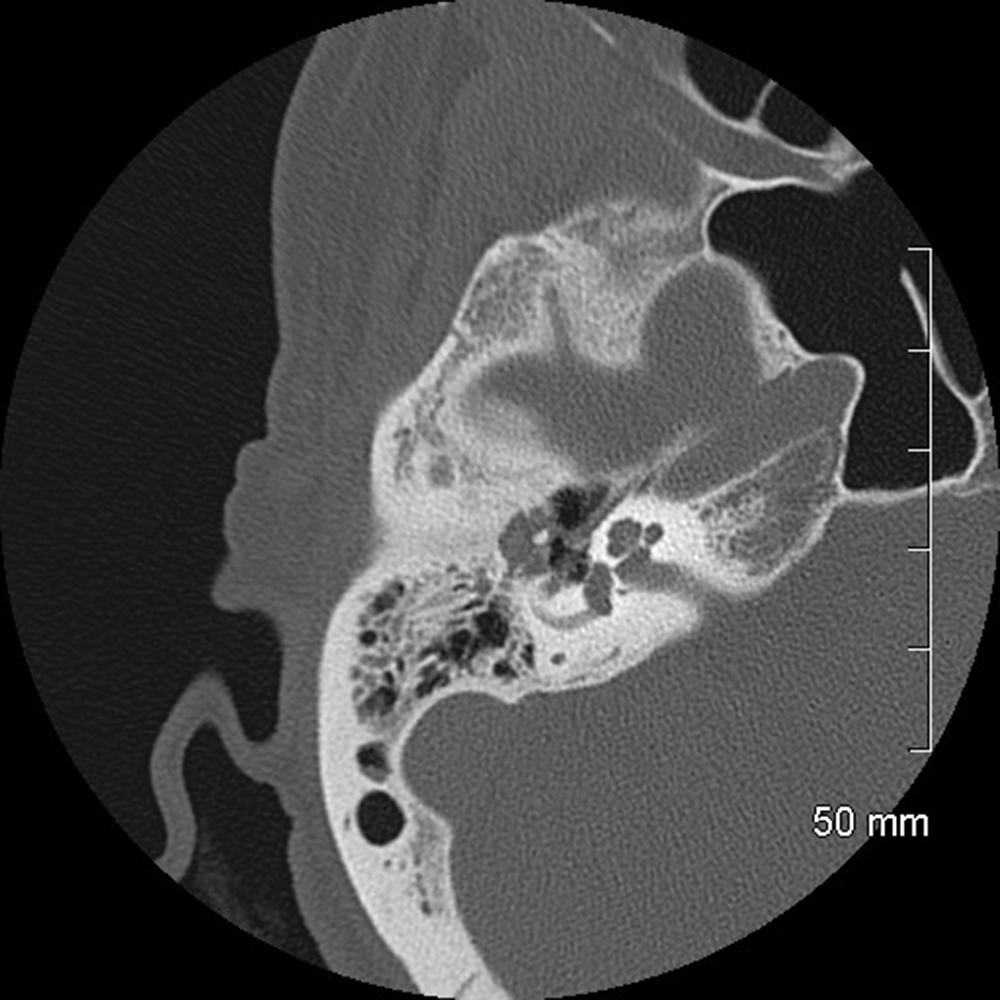

Hearing loss can be caused by diseases of the external, middle, or inner ears leading to either a conductive, sensorineural, or mixed dysfunction. Imaging plays a central role in the management of these conditions by providing important diagnostic clues and detailed information to help medical and/or surgical treatment. This session offers an overview of these disease conditions and discusses important points that assist diagnosis.